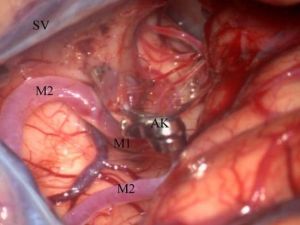

Konuşurken Beynindeki Tümör Alındı